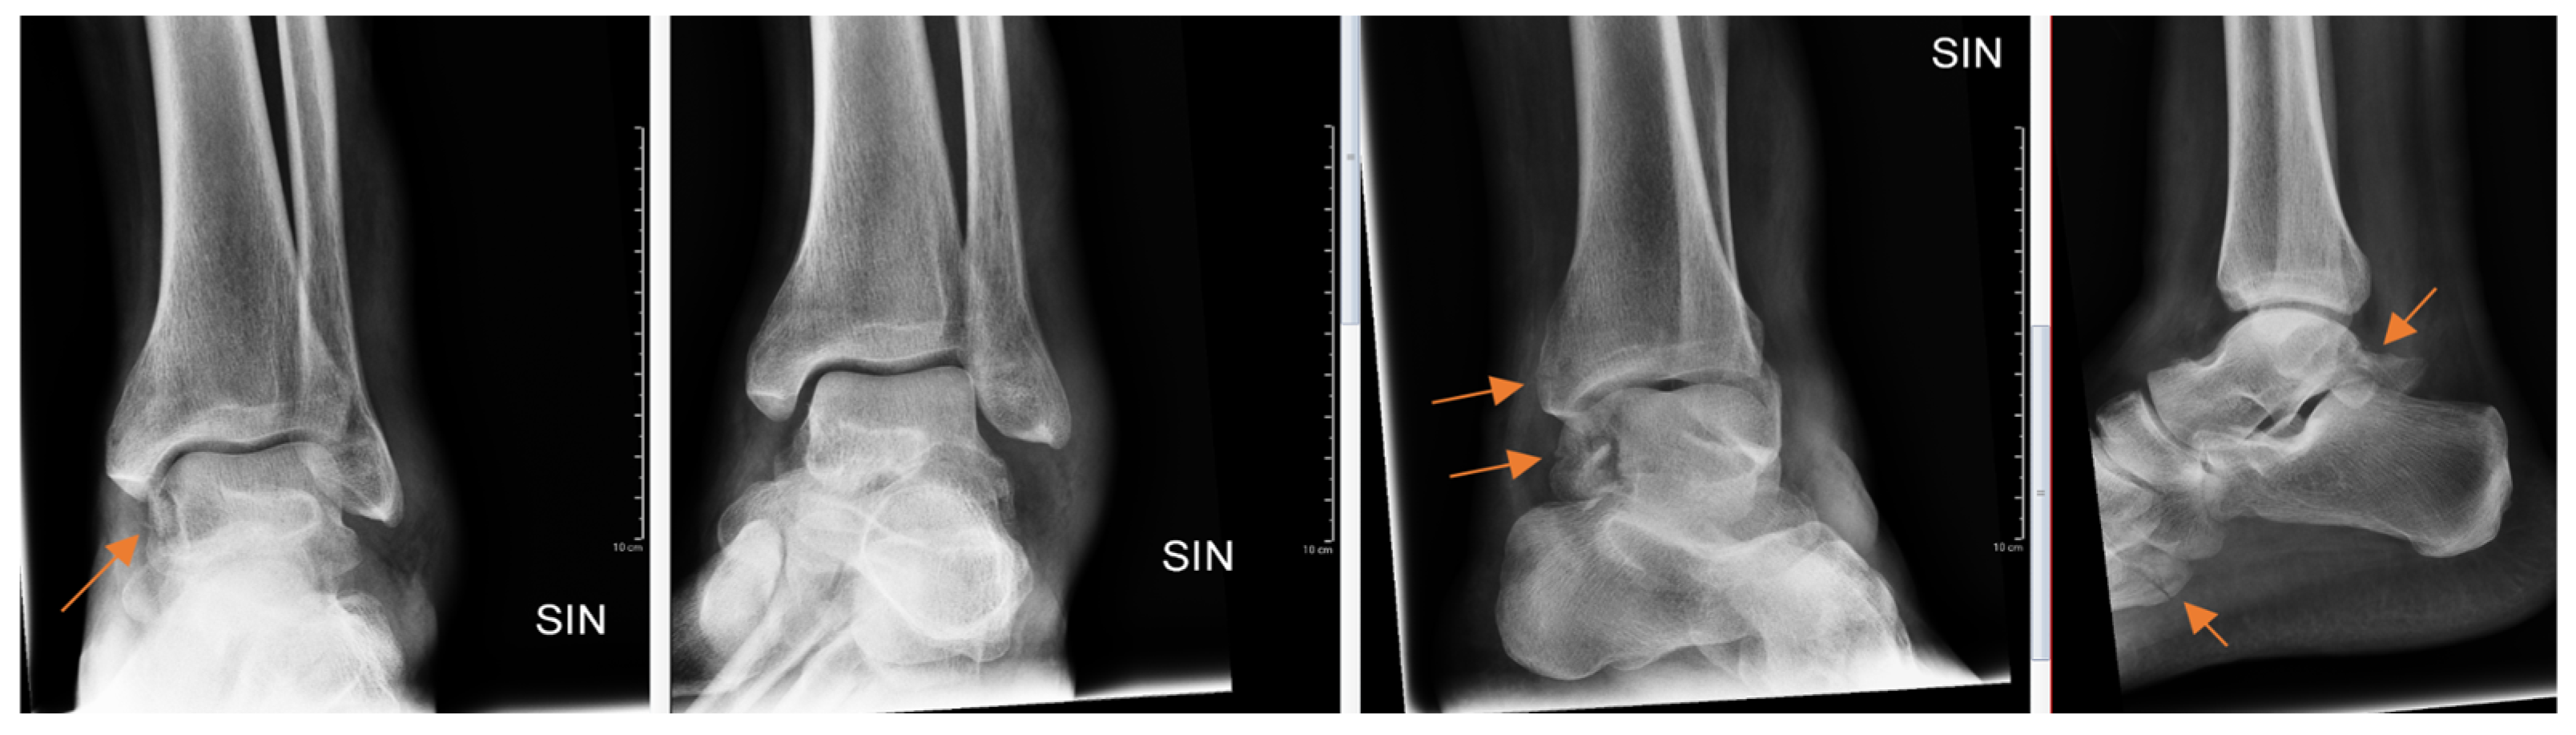

Figure 3.

Patient with ankle trauma. Multiple obvious findings (arrows) in radiographs that were all missed by the resident.